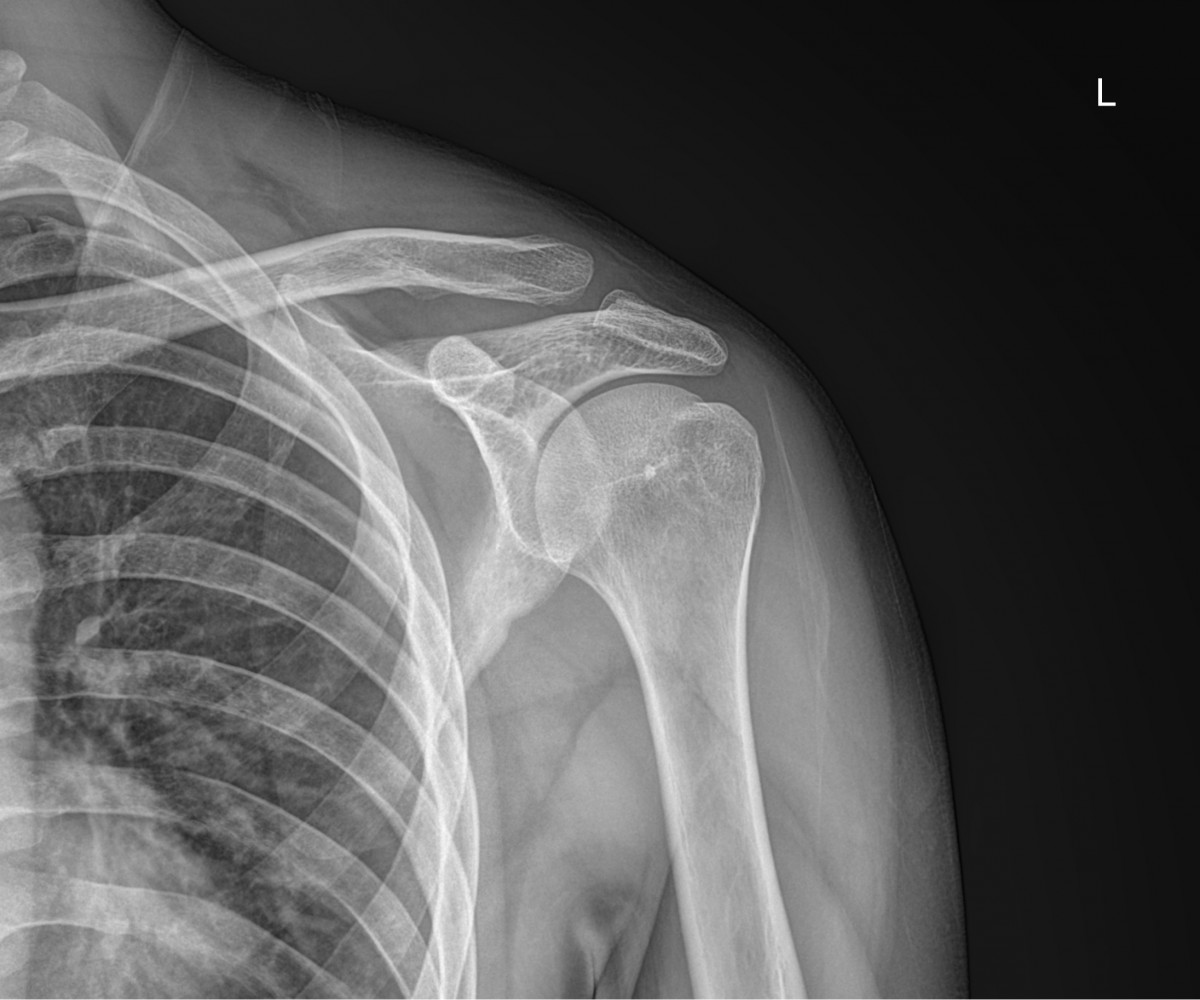

이재상원장님 어깨 골절 수술 김시O 환자

dae765e4d9ac96aee867c9d6292d8784_1758001812_7852.jpg